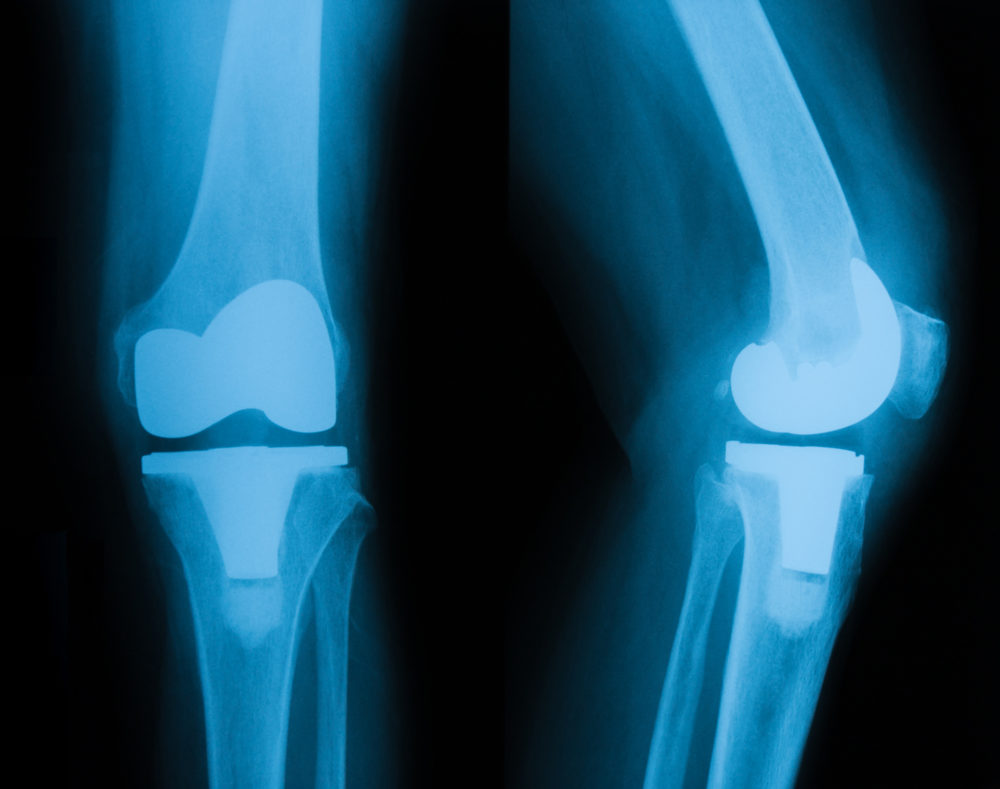

وأوضح أن عملية تعديل مراكز النمو، تسمى أيضا بعملية تعديل سرعات النمو، وتعد من أكثر أنواع العمليات التي تستخدم من أجل علاج تقوس الساقين، حيث يتم تركيب شريحة صغيرة ومسمارين على طول صفائح النمو التي توجد في نهاية العظام، مؤكدا أن هذا الجزء يعد المسئول عن زيادة طول عظام الطفل، فعندما يتم تركيب الشريحة فإن هذا يؤدي إلى تبطئ عملية النمو في جانب واحد، مما ينتج عنه تصحيح وضع الساقين وعلاج التقوس.

وأوضح أن عملية قطع عظم قصبة الساق يعد أحد أنواع علاج تقوس الساقين، فهو عبارة عن شق عظمي في قصبة الساق، والتي تكون أسفل الركبة مباشرة، حيث يتم تثبيت عظمة الساق في وضعها السليم، وذلك من خلال وضع جهاز مثبت خارجي، أو يتم وضع شريحة داخلية بها مسامير طبية.